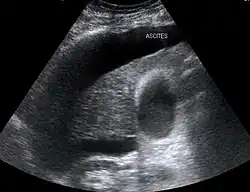

HRS can affect individuals with cirrhosis, severe alcoholic hepatitis, or liver failure, and usually occurs when liver function deteriorates rapidly because of a sudden insult such as an infection, bleeding in the gastrointestinal tract, or overuse of diuretic medications. HRS is a relatively common complication of cirrhosis, occurring in 18% of people within one year of their diagnosis, and in 39% within five years of their diagnosis. Deteriorating liver function is believed to cause changes in the circulation that supplies the intestines, altering blood flow and blood vessel tone in the kidneys. The kidney failure of HRS is a consequence of these changes in blood flow, rather than direct damage to the kidney. The diagnosis of hepatorenal syndrome is based on laboratory tests of individuals susceptible to the condition. Two forms of hepatorenal syndrome have been defined: Type 1 HRS entails a rapidly progressive decline in kidney function, while type 2 HRS is associated with ascites (fluid accumulation in the abdomen) that does not improve with standard diuretic medications.

Both types of hepatorenal syndrome share three major components: altered liver function, abnormalities in circulation, and death. As these phenomena may not necessarily produce symptoms until late in their course, individuals with hepatorenal syndrome are typically diagnosed with the condition on the basis of altered laboratory tests. Most people who develop HRS have cirrhosis, and may have signs and symptoms of the same, which can include jaundice, altered mental status, evidence of decreased nutrition, and the presence of ascites.[2] Specifically, the production of ascites that is resistant to the use of diuretic medications is characteristic of type 2 HRS. Oliguria, which is a decrease in urine volume, may occur as a consequence of kidney failure; however, some individuals with HRS continue to produce a normal amount of urine.[3] As these signs and symptoms may not necessarily occur in HRS, they are not included in the major and minor criteria for making a diagnosis of this condition; instead HRS is diagnosed in an individual at risk for the condition on the basis of the results of laboratory tests, and the exclusion of other causes.[3]